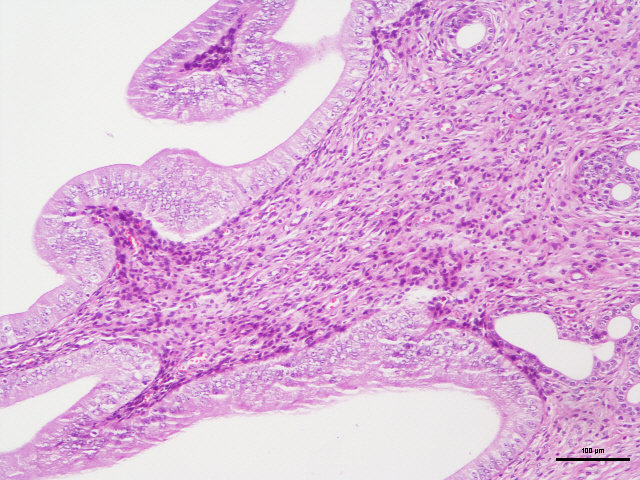

病理学的所有切片,都必须通过一种以上的染料,通过各种不同的方法,将切片中各种不同的物质,在不同染液的作用下,将其显示出来,使之在光学显微镜下,能够完全的观看各种结构。例如,HE染色,好质量的切片可以清晰地显示出许多不同的结构,细胞核着蓝黑色,细胞浆着粉红色,软骨着蓝色等。清晰的结构为诊断提供可靠的依据,因此,染色技术也是病理技术中的重要组成部分,必须不断地总结,方能提高。如果染色不好,切片染色一团糟,红蓝不分,结构不清,层次不明,影响了镜下的观察,直接影响了临床诊断,染色结果的好坏直接关系到诊断的准确性。

(25)中性树胶封固。结果:细胞核被染成深蓝黑色;细胞浆被染成粉红色;软骨及钙盐被染成蓝色;胶原纤维染成淡粉红色,嗜酸性细胞及嗜酸性颗粒呈鲜红色;弹力纤维呈淡粉红色;某些蛋白性物呈粉红色等。

样片参考:

肠

胃

子宫

HE染色 | 染色含切片 | 苏木.精-伊红染色法,观察组织形态 |